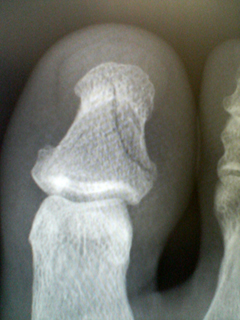

写真では軽くヒビくらいに見えますが、横から見ると意外に線が沢山入ってまして、お医者さんは「折れたっていうよりは『潰れた』って感じだね」って仰ってました、、、てへっ。

ご存知の方も多いと思いますが、「右足の親指」はバスドラムを踏むのに非常に重要な部位でして、回復を早める為に安静&禁酒していた訳でございます。。。その甲斐あってか非常に順調に治りまして、3週後から既にドラムを叩く事が出来ました!

演奏後はまだ若干の違和感がありますけど、もうほとんど問題なく演奏出来ます。ご心配おかけしましたが、もう大丈夫です。ありがとうございました。。。